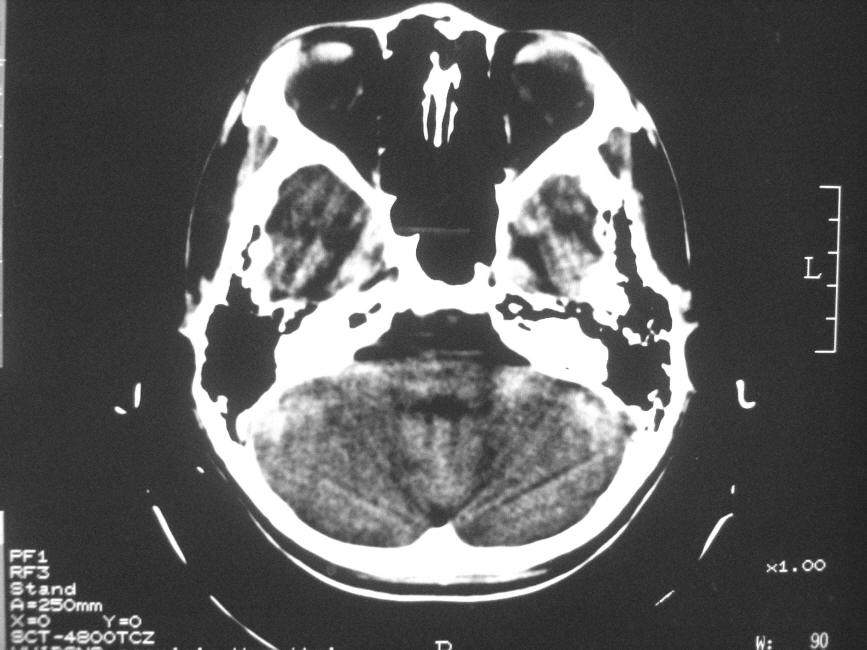

以下是引用zzyy在2008-6-16 10:13:00的发言:[br]两侧脑白质呈对称性密度减低,病儿有发热及脑膜刺激征。考虑急性病毒性脑炎。